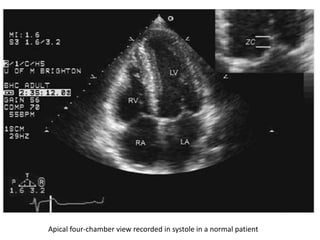

Apical four-chamber view recorded in systole in a normal patient

Apical four-chamber viewrecorded in systole in a normal patient

• #27 Apical four-chamber view recorded in systole in a normal patient. In this image, the normal closure pattern of the anterior and posterior leaflets of the mitral valve is clearly demonstrated. At the upper right, the closure pattern has been expanded. Note that the anterior and posterior mitral valve leaflets do not close tip to tip but rather along a 4-mm length [the zona coapta (ZC)].